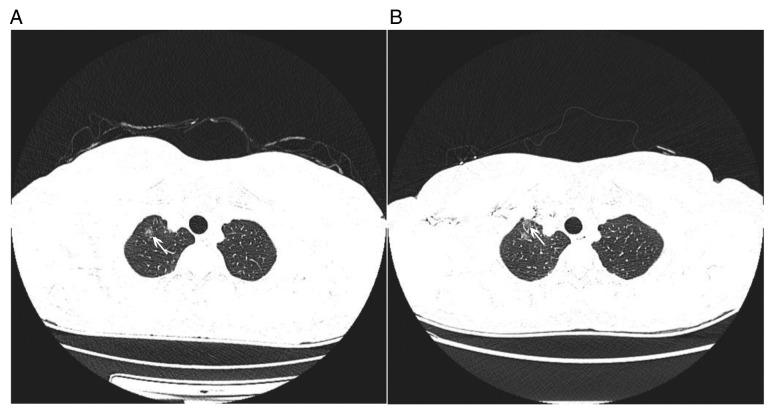

采用非增强和对比增强CT纹理分析识别表现为磨玻璃密度结节的肺腺癌:一项回顾性分析。

Pulmonary adenocarcinoma appearing as ground-glass opacity nodules identified using non-enhanced and contrast-enhanced CT texture analysis: A retrospective analysis.

The present study aimed to investigate the ability of CT-based texture analysis to differentiate invasive adenocarcinoma (IA) from pre-invasive lesions (PIL) or minimally IA (MIA) appearing as ground-glass opacity (GGO) nodules, and to further compare the performance of non-enhanced CT (NECT) images with that of contrast-enhanced CT (CECT) images. A total of 77 patients with GGO nodules and surgically confirmed pulmonary adenocarcinoma were included in the present retrospective study. Each GGO nodule was manually segmented and its texture features were extracted from NECT and CECT images using in-house developed software coded in MATLAB (MathWorks). The independent-samples ttest was used to select the texture features with statistically significant differences between IA and MIA/PIL. Multivariate logistic regression and receiver operating characteristics (ROC) curve analyses were performed to identify predictive features. Of the 77 GGO nodules, 12 were atypical adenomatous hyperplasia or adenocarcinoma (15.6%), 36 were MIA (46.8%) and 29 were IA (37.7%). IA and MIA/PIL exhibited significant differences in most histogram features and gray-level co-occurrence matrix features (P<0.05). Multivariate logistic regression and ROC curve analyses revealed that smaller energy and higher entropy were significant differentiators of IA from MIA and PIL, irrespective of whether NECT images [area under the curve (AUC): 0.839, 0.859] or CECT images (AUC: 0.818, 0.820) are used. Texture analysis of CT images, regardless of whether NECT or CECT is used, has the potential to distinguish IA from PIL or MIA, particularly the parameters of energy and entropy. Furthermore, NECT images were simpler to obtain and no contrast agent was required; thus, analysis with NECT may be a preferred choice.

摘要